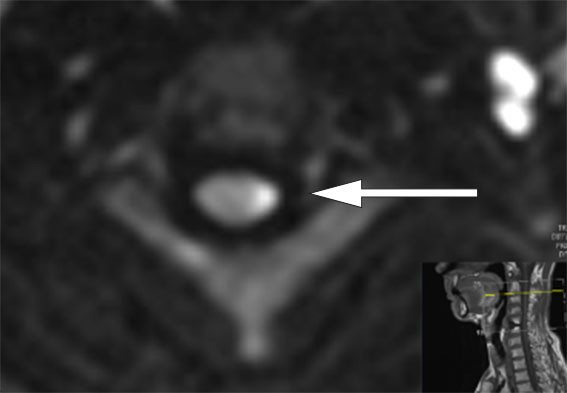

MR-undersøkelsen av hjernen viste funn forenlig med et lite, ferskt infarkt i venstre cerebellarhemisfære. Intramedullært var det nå tilkommet et mer distinkt, økt T2-signal i nivå C2–C4 (figur 1), der aksialt diffusjonsopptak viste restriktiv diffusjon innad i områder med økt T2-signal, som hadde overvekt mot venstre side (figur 2).